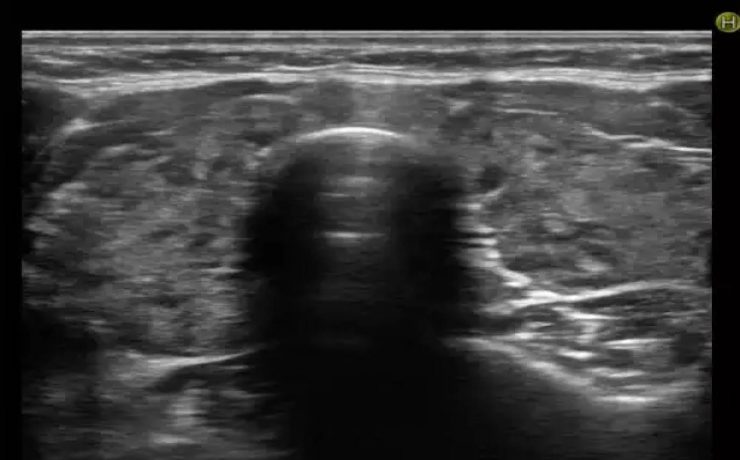

En este estudio se analiza la utilidad del ultrasonido en el estudio de la paciente estéril, específicamente con ultrasonido con aplicación de doppler, de Power doppler y la ecografía 3D para analizar los cambios cualitativos y cuantitativos que se observan en la irrigación del ovario en pacientes estériles, en pacientes